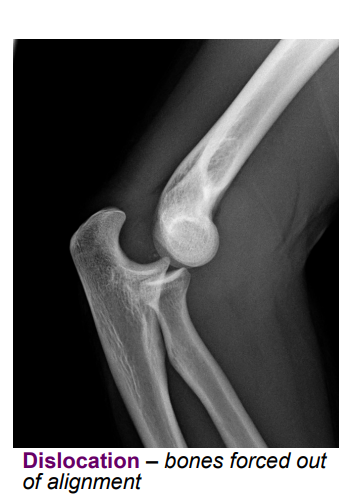

Define the following and give common causes of each: Dislocation

reduction = moving bones back into alignment

<p>reduction = moving bones back into alignment</p><p></p>